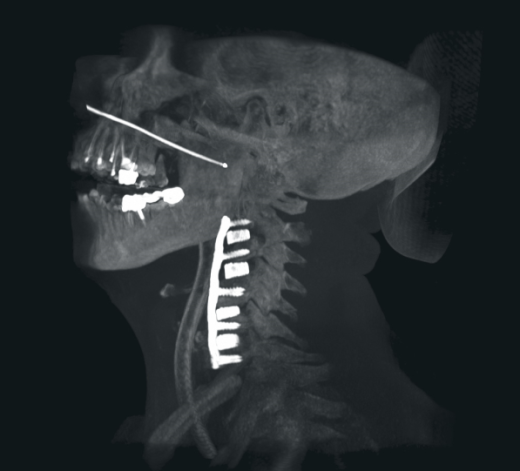

- нейрохирургия,

В ходе проведения рентгенохирургических вмешательств хирург имеет возможность на референтном мониторе рабочей станции осуществлять просмотр и обработку только что полученных 3D изображений, выполнять реконструкцию полученных данных для получения объемных изображений различного разрешения и размера поля, проводить измерения в ортогональных проекциях, выбирать оптимальный угол доступа.

Синхронизация с системами стереотаксической навигации

Возможность оправки 3D изображений на стереотаксические системы Bainlab, Medtronic, Stryker для проведения хирургических вмешательств с использованием нейронавигации с минимальной погрешностью смещения.